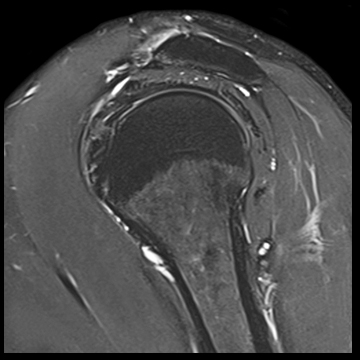

肩関節

T1 TSE FatSat,

T2 TSE FatSat,

T2 TSE,